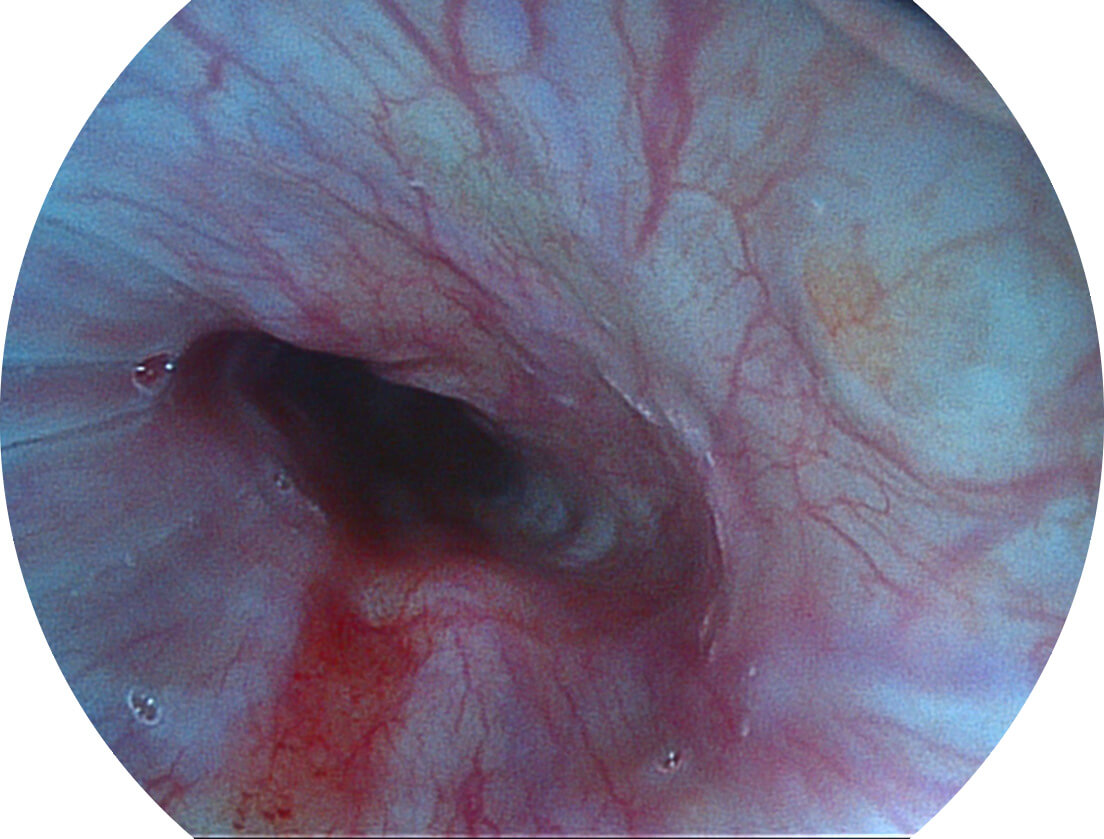

SFI图像

图像具有高亮度、高黏膜血管颜色对比度的特点,且不改变粘液、食物残渣、粪便的基本颜色,可在中远景下进行观察,助力消化道早期疾病的诊断。